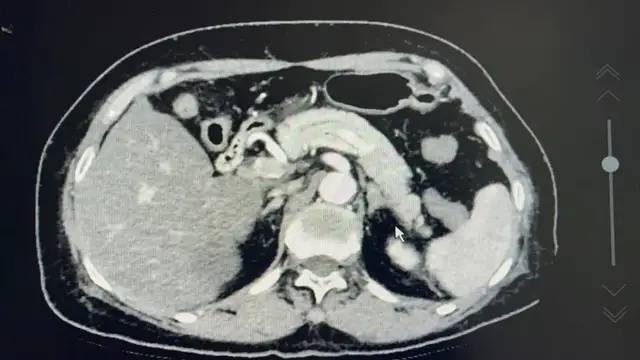

在完善一系列继发性高血压的相关检查后 , 原发性醛固酮增多症诊断明确 , 肾上腺增强CT显示 , 双侧肾上腺增厚 , 左侧肾上腺腺瘤 。